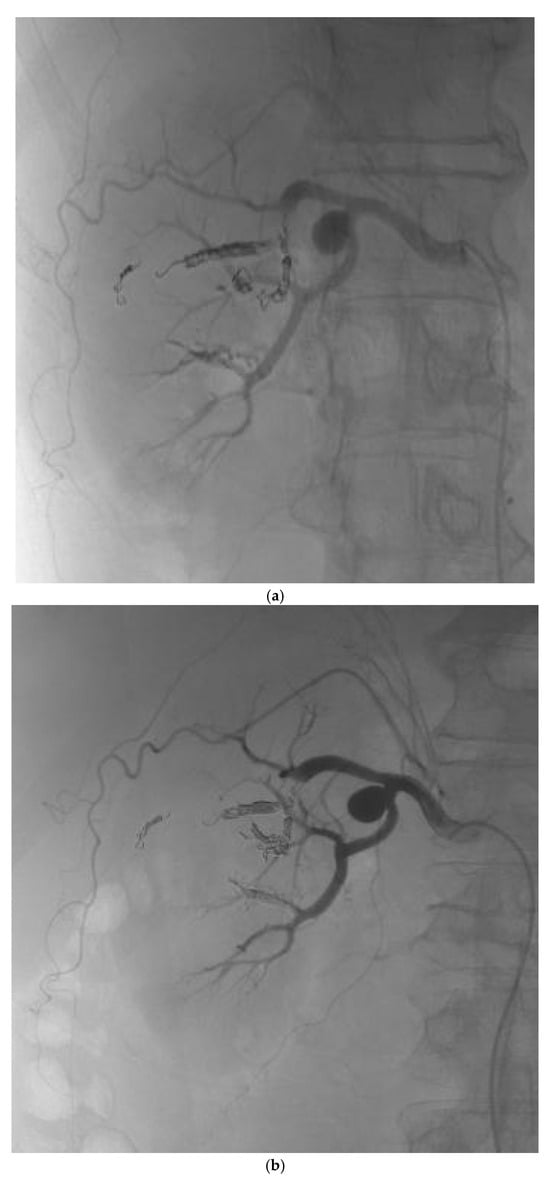

During hospitalization, he received antibiotics and underwent cystoscopy with evacuation of bladder clots. CT angiography confirmed the AVM (Figure 1a) and selective angioembolization was performed via a left femoral approach (Figure 1b). Post-procedure angiography demonstrated complete occlusion of the AVM nidus (Figure 2a) with preserved perfusion of the remaining renal vasculature (Figure 2b). At discharge, he was clinically stable, with normalized creatinine and clear urine. The administered therapy during hospitalization and subsequent follow-up is outlined in Table 2. After discharge, the patient was prescribed fosinopril (Monopril) 10 mg twice daily, titrated to the maximally tolerated dose and empagliflozin 10 mg once daily. Follow-up visits were scheduled at 6 and 12 months after embolization as determined by the attending nephrologist, consistent with routine monitoring intervals for renal recovery and therapy adjustment in clinically stable patients.

Figure 2. (a) Post-procedure angiogram of the right renal artery showing complete occlusion of the AVM nidus. (b) Post-procedure angiogram demonstrating preserved blood flow in the remaining arterial vasculature of the right kidney.